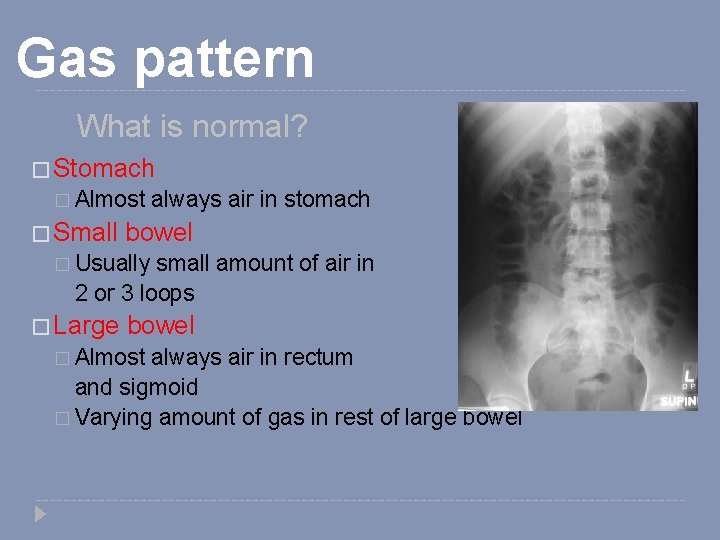

Gas pattern What is normal? � Stomach � Almost � Small always air in stomach bowel � Usually small amount of air in 2 or 3 loops � Large bowel � Almost always air in rectum and sigmoid � Varying amount of gas in rest of large bowel